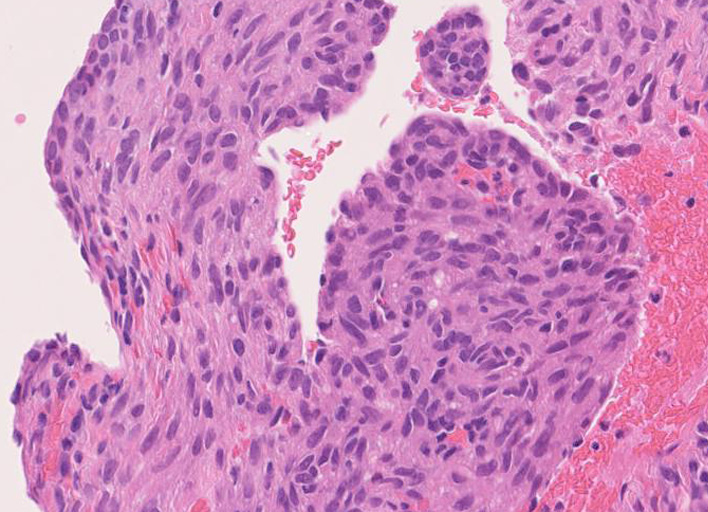

LAMの肺病変

嚢胞周囲または肺血管, リンパ管, 細気管支にそうLAM cellの浸潤, 集簇を特徴とする。LAM cellには2種類が認められ, 小型紡錘形細胞と細胞質の豊富な類上皮様細胞があり, 紡錘型は主に集簇巣の中心に存在し増殖能が高い。 類上皮様LAM cellは辺縁部に多く, 増殖能は低いがHMB45を強く発現している。

嚢胞形成はLAM cellの増殖と関連しており, 細胞が産生するmatrix metalloproteinases(MMPs)による組織破壊によるらしい。